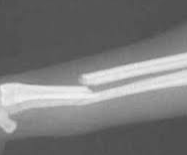

犬の腓骨は、豚と同様、全長にわたって独立した完全な骨ですが、体重を負担する役割をほとんど演じていないので、骨折がおこっても、特に治療をほどこすことはありません。

脛骨の骨折と合併した場合にも、手術的治療は脛骨に対してのみ行われます。